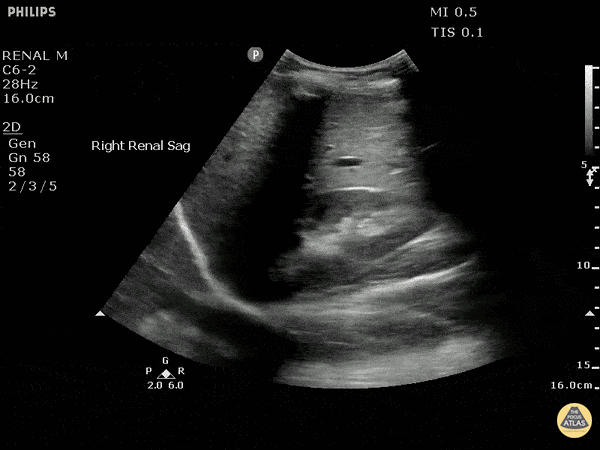

This patient presented with hematuria and flank pain. In this scan, you can see a visible circular mass along the inferior pole of the kidney with further testing later confirming presence of a renal cell carcinoma. Image courtesy of Robert Jones DO, FACEP @RJonesSonoEM Director, Emergency Ultrasound; MetroHealth Medical Center; Professor, Case Western Reserve Medical School, Cleveland, OH View his original post here